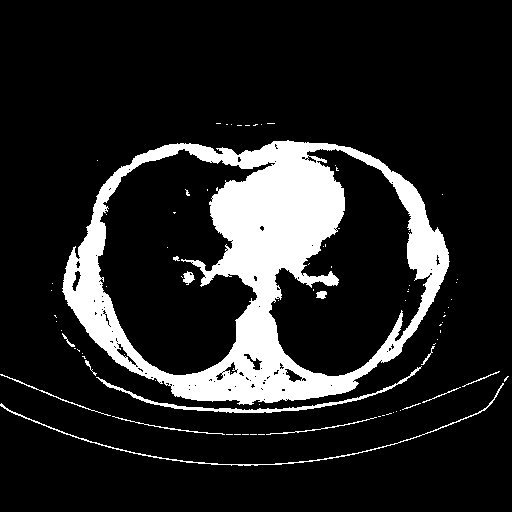

Original NATIVE CT scan (input)

Full window (WL 1023.5, WW 4095 β†’ Low βˆ’1024, High +3071)

Actual HU range: [-1024.0, 3071.0]